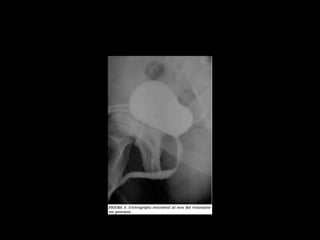

• Estudio elección: cistograma de llenado 350-

400ml solución salina, con 4% de contraste a

una altura de infusión de 40 cm.

Diagnostico

• Cystography: Gold standard

• CT Cystography : New trend

• Peng et al. AJR 2011.

– Prospective study

– 305 patients.

– Cystography VS. CT cystography

– Ruptures confirmed by Surgery

– 100% sensitive and specific